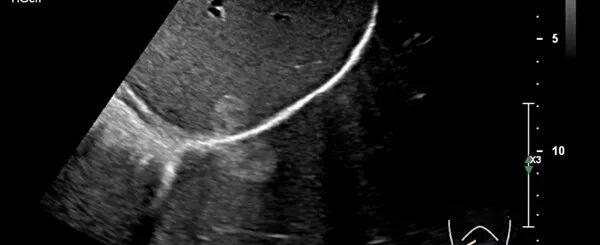

声影

声影是较常见的伪像之一,其发生是因为在超声扫描成像中,当声束遇到强反射(如含气肺)或声衰减程度很高的物资(如瘢痕、结石、钙化等)时,声束被完全遮挡而在其后方出现条带状无回声区即为声影。

声影对识别瘢痕、结石、钙化和骨骼时很有帮助。